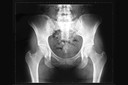

Os ossos mais frequentemente afetados incluem costelas30, fêmur28, tíbia31, ossos craniofaciais e pelve32, enquanto o envolvimento das mãos33, coluna e esterno34 é menos comum.

O diagnóstico25 baseia-se principalmente em exames de imagem, associados à avaliação clínica. A radiografia simples é geralmente o exame inicial e pode mostrar uma lesão23 com aspecto clássico em “vidro fosco”, associada à expansão óssea, adelgaçamento cortical e deformidade estrutural, sem características agressivas típicas de tumores malignos.

Radiologicamente, a lesão23 apresenta frequentemente o aspecto clássico em “vidro fosco”, devido à mistura de matriz fibrosa e mineralização incompleta, embora esse padrão possa variar conforme a idade do paciente e a fase evolutiva da lesão23.